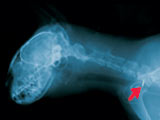

Der Transponder hat etwa die Größe eines Reiskorns und enthält einen elektronischen Chip mit dem Identifizierungscode.

Jede dieser 10–stelligen Kombinationen ist einmalig und kann nicht geändert werden. Mit einer Spritze wird der Transponder ins Gewebe (zum Beispiel im Nackenbereich) injiziert, wo er ein Leben lang bleibt. Da er nicht mit dem umgebenden Gewebe reagiert und auch nicht im Körper wandert, ist er für das Tier völlig unschädlich.